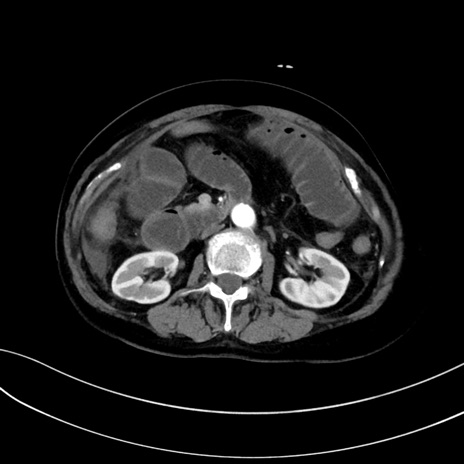

症例13 CT(横断像)1日半後